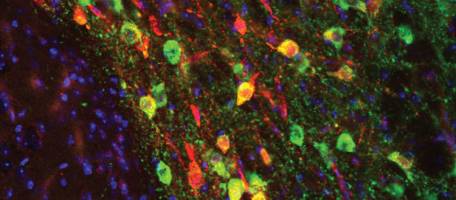

Les troubles du spectre autistique constituent un groupe hétérogène de troubles neurodéveloppementaux, dont l'une des caractéristiques principales est l'altération de la communication sociale. Mais que se passe-t-il dans le cerveau des patients pour que leurs compétences sociales soient ainsi perturbées - Un mauvais fonctionnement de l'activité synaptique d'un type de neurones présents dans le système de la récompense semble être en cause, selon des scientifiques des Universités de Genève (UNIGE) et de Bâle (UNIBAS), dont les travaux sont publiés dans la revue Nature Communications .